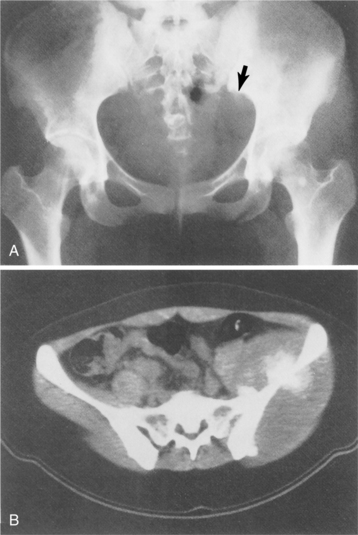

CT scans and especially MRI are used to evaluate the extent of disease. In Fig. 26-7 plain films of a pelvis demonstrate minimal changes that could easily be dismissed as insignificant. The CT scan, however, reveals a large osteosarcoma involving the ilium. More commonly, radiographs show a rapidly growing lesion with poorly defined margins, and a permeated or moth-eaten appearance in the lytic area.

Figure 26-7 Osteosarcoma. A, A subtle sclerotic lesion is seen in the left ilium adjacent to the sacroiliac joint that was initially diagnosed as osteitis condensans ilii, a benign entity. Because of persistent pain, the person returned for a follow-up visit, and a small amount of cortical destruction on the pelvic brim was noted (arrow). B, A computed tomographic scan was performed, which showed a large tissue mass and new bone tumor around the ilium, which is characteristic of an osteogenic sarcoma. (From Helms C: Fundamentals of skeletal radiology: benign cystic lesions, Philadelphia, 1989, WB Saunders.)